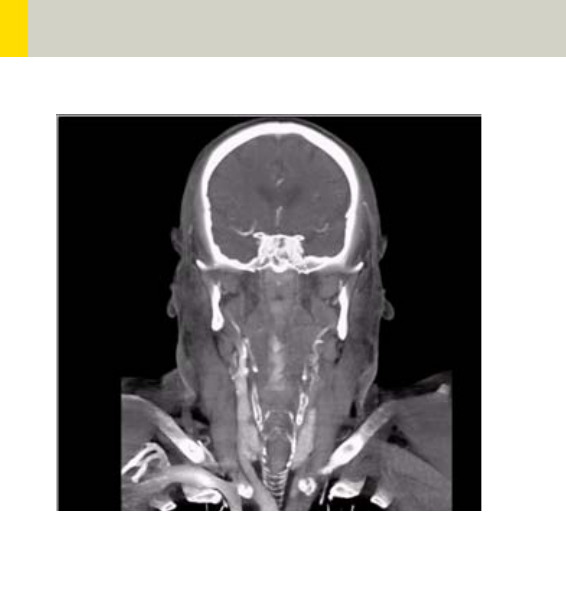

Principle of automatic tube current adaptation by

CARE Dose 4D for a spiral scan from shoulder to pelvis

(very high table feed for demonstration): High tube

current and strong modulation in shoulder and pelvis,

lower tube current and low modulation in abdomen

and thorax. The dotted lines represent the min. and

max. tube current at the corresponding table position

and result from the attenuation profile of the Topo-

gram.

The mAs value displayed in the user interface and in

the patient protocol is the mean (eff.) mAs value for

the scan range.

The mAs value recorded in the images is the local (eff.)

mAs value.